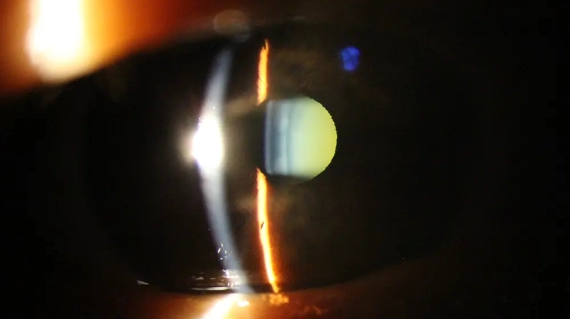

No astigmatismo, a focalização da imagem ocorre sobre mais de um plano, assim podem ocorrer distorções ou embaçamento em partes da imagem. Pode existir como erro refracional único ou associado a miopia ou hipermetropia.